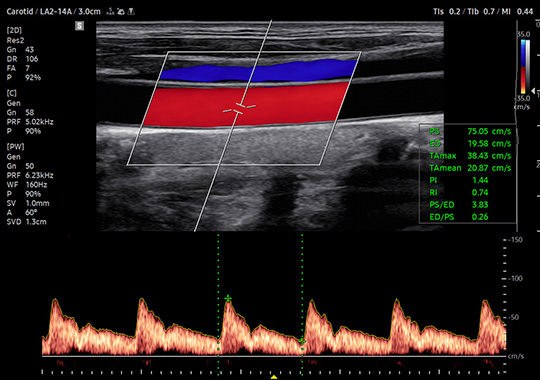

LA2-14A

- Wide Band Linear

- Application: Abdomen, Musculoskeletal, Pediatric, Small Parts, Thoracic, Vascular